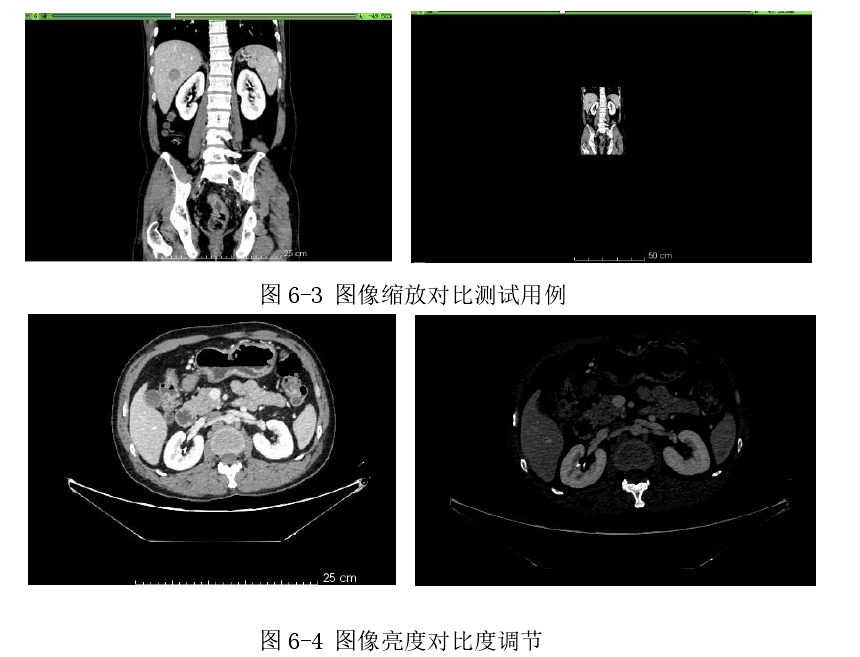

6.2.2 图像鼠标操作测试

本系统通过鼠标键盘响应事件,来实现图像缩放功能如图(图 6-3)以及图像亮度对比度的调整(如图 6-4)。具体做法是:鼠标停留在切片视图时,按住 ctrl 鼠标上下滑动实现图像缩放。鼠标停留在切片视图时,按住鼠标按住左键上下/左右滑动来实现亮度/对比度调整。